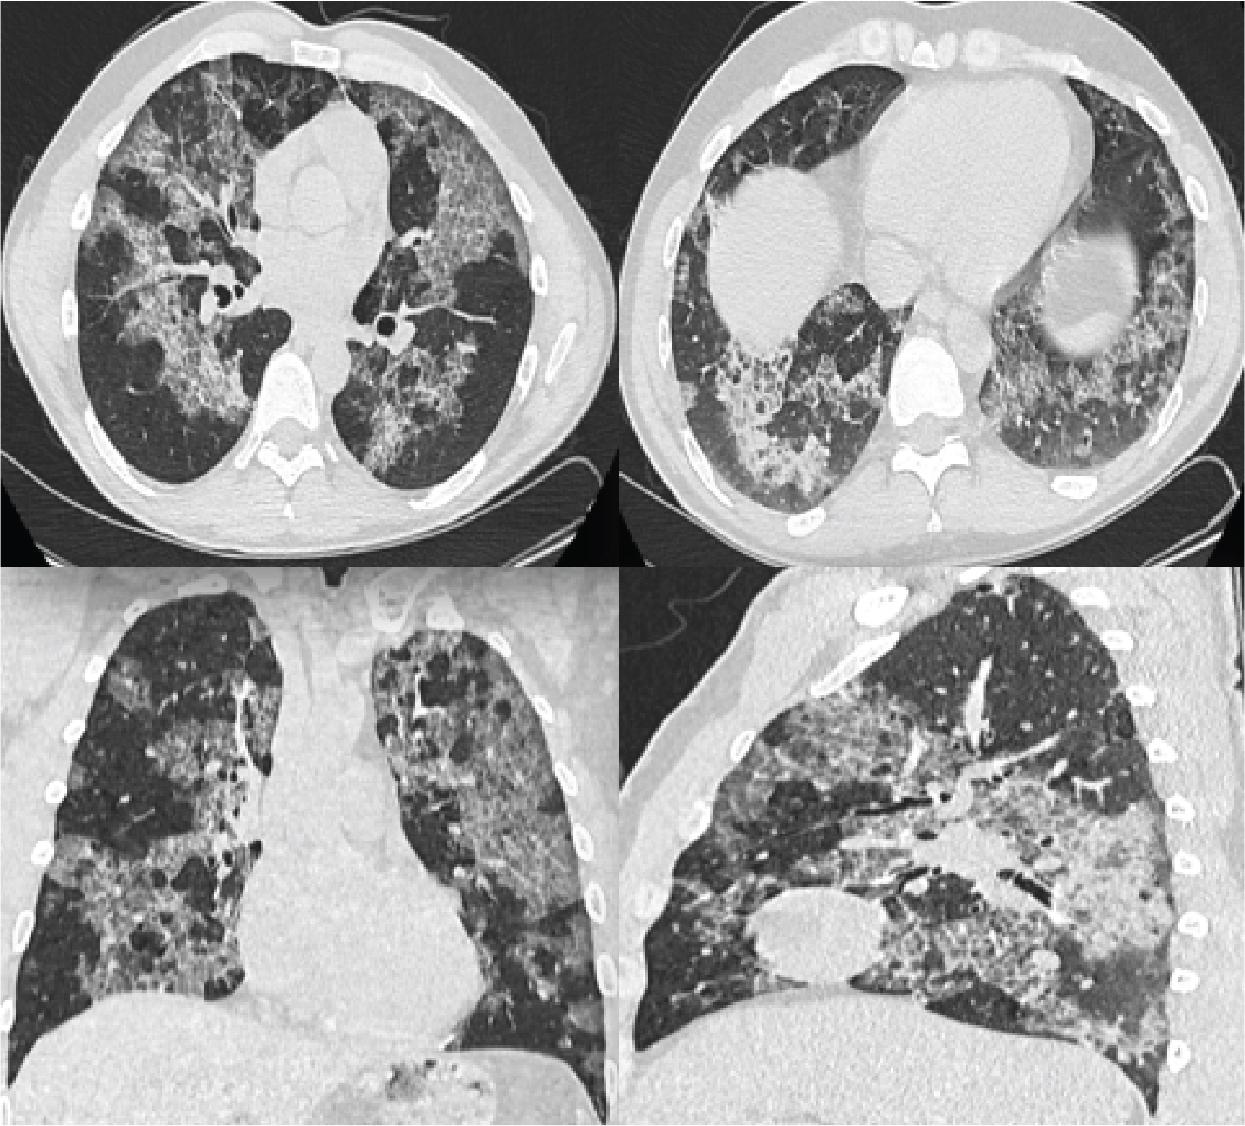

From a biological point of view, all parameters are within normal limits and without inflammatory markers. HRCT of the native chest is performed. Compared with the initial Computed Tomography (CT) scan (Figure 1), it suggests a stable imaging appearance, with the persistence of diffuse ground-glass opacities and extensive plaques of pulmonary condensation, with a mixed alveolar-interstitial pattern and mosaic appearance of bilateral crazy-paving, without overadded enlarged lesions.

Computer tomography was performed initially.